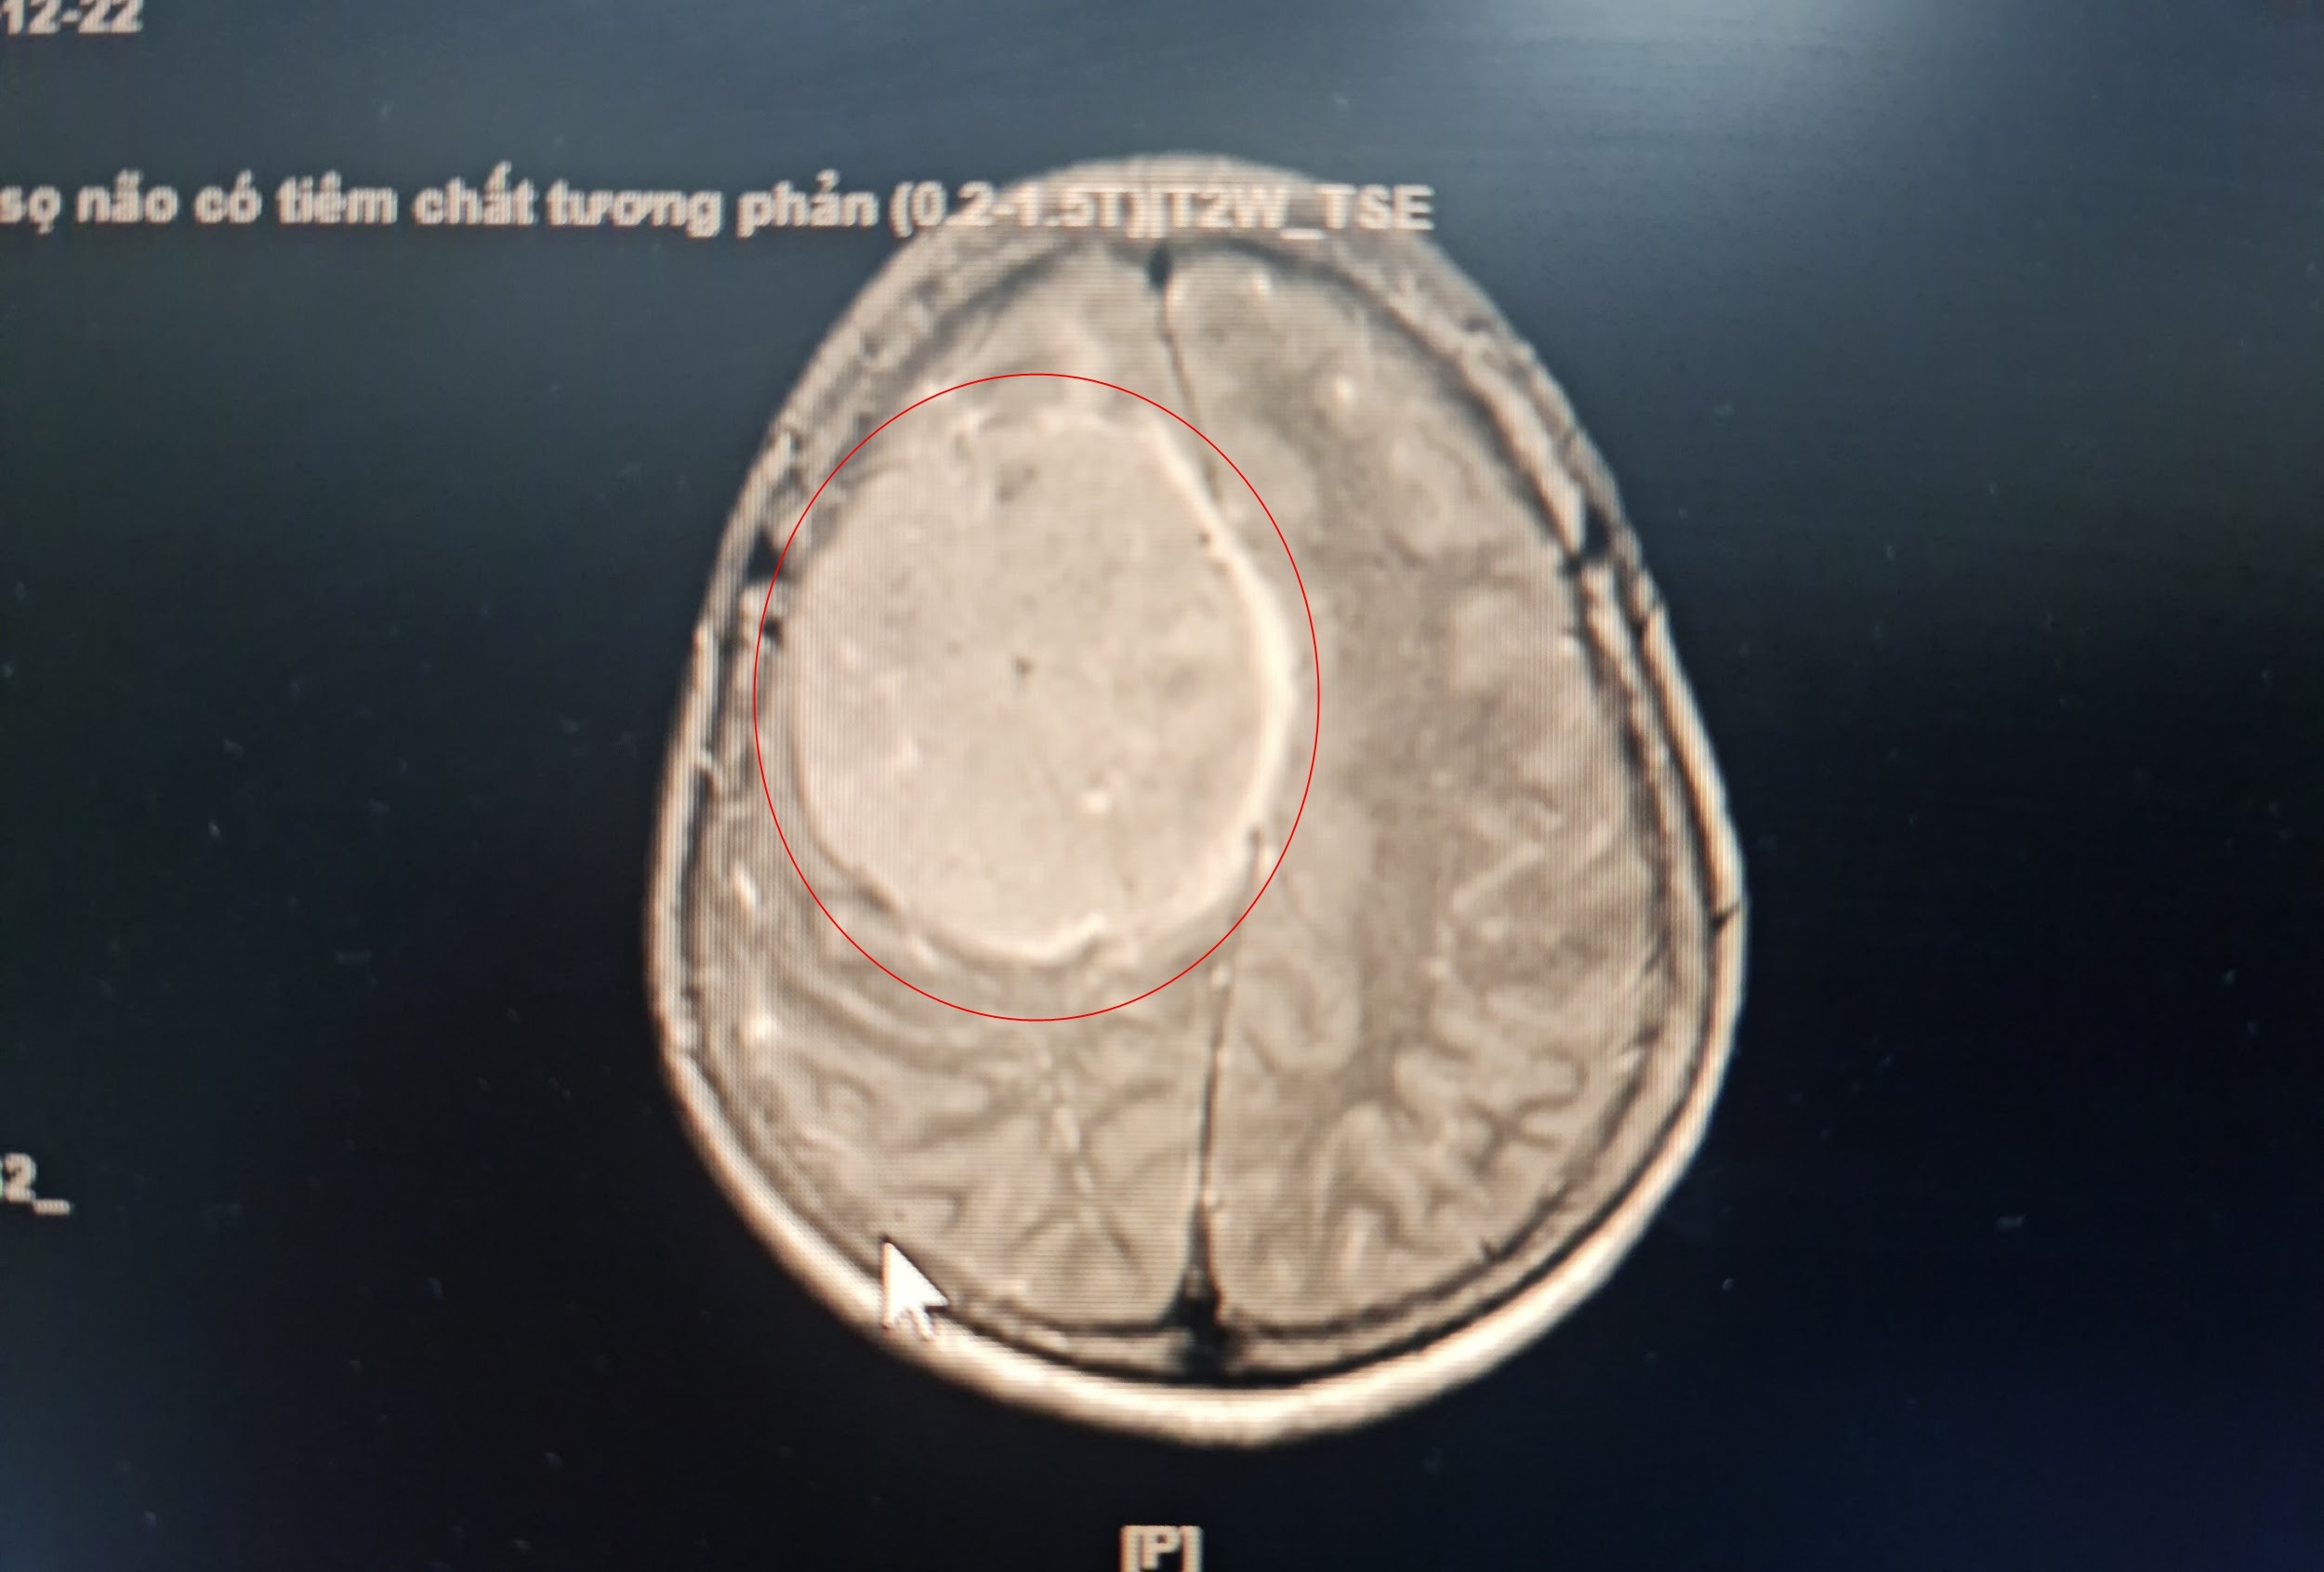

Khối u não phát triển lớn, chèn 1/4 diện tích não của bệnh nhân. Ảnh: BVCC.

Khối u màng não của bà T. có kích thước 7x8 cm. Nghiêm trọng hơn, khối u này nằm sát, xâm lấn xoang tĩnh mạch dọc giữa và một phần xương sọ, gây chèn ép 1/4 não và phù não xung quanh.